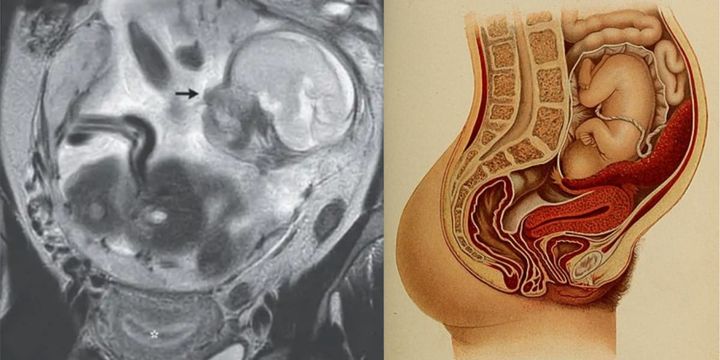

子宮に胎児がいない⁈ 「腹腔で赤ちゃんを妊娠」した極めて稀なケースが報告される / Credit: Guillaume Gorincour et al., The New England Journal of Medicine(2023), Wikimedia Commons

腹腔で発育していた胎児の画像(その下の星印で示されたのが子宮)

腹腔で発育していた胎児の画像(その下の星印で示されたのが子宮) / Credit: Guillaume Gorincour et al., The New England Journal of Medicine(2023)

おそらく、女性が訴えていた腹痛は、腹腔内で大きくなった胎児が周りの臓器を圧迫していたからだと考えられます。

胎児は羊水の入った羊膜に包まれており、へその緒もつながっていて、正常に発育しているようでした。

また通常は子宮内にできるはずの「胎盤」も胎児とともに腹腔にあり、女性の背骨の付け根近くの腹部内壁に付着していたようです。